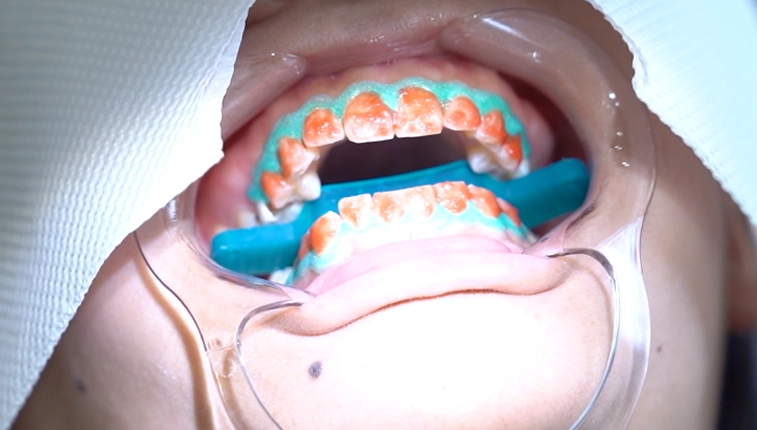

step.3

薬剤の塗布

最初に歯ぐきにお薬がつかないように歯ぐきを保護していきます。ホワイトニングで使用する薬剤を歯の表面に塗り、5分間放置します。

step.4

光の照射

歯の表面に薬剤を塗ったら、専用の光を3分間照射していきます。コンパクトながら光を正確に歯の表面に照射することができ、優れたパワーを発揮します。光照射後、7分間放置します。その後、薬剤を除去していきます。この工程が1setです。(1setの時間/15分)キャンペーンの費用は1set1回です。